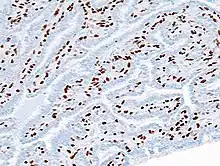

| Histopathology of intraductal papilloma of the breast by excisional biopsy. Immunostaining for p63 protein. | |

Histopathology of intraductal papilloma of the breast by excisional biopsy. Hematoxylin and eosin stain.- Histopathology of intraductal papilloma of the breast by excisional biopsy. Immunostaining for alpha-smooth muscle actin.